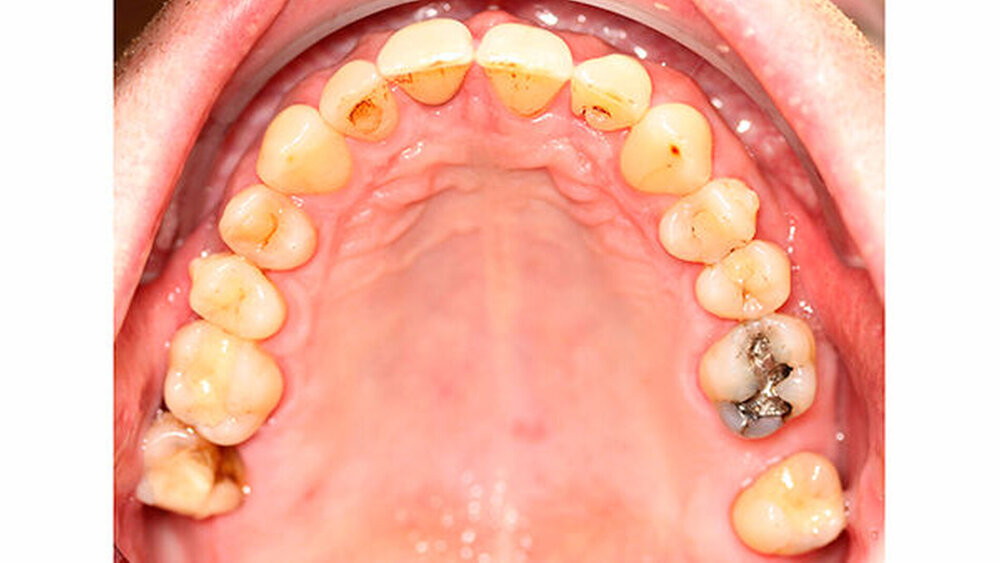

Um einen kompletten Lückenschluss im Oberkiefer zu ermöglichen, musste im Unterkieferfrontzahnbereich zusätzlich zur Derotation und Positionierung der Zähne - insbesondere Zahn 41 - von approximaler Schmelzreduktion, kurz ASR , Gebrauch gemacht werden, um einer Tonn`schen Diskrepanz entgegenzuwirken (Abbildung 4).